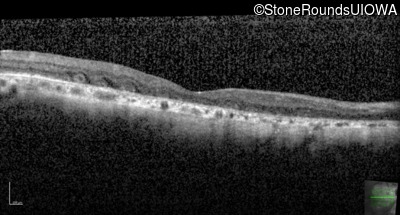

Age at visit: 55 years

Age at visit: 56 years

Age at visit: 57 years

Age at visit: 57 years (Visit 2)

Age at visit: 57 years (Visit 3)

Age at visit: 57 years (Visit 4)

Age at visit: 58 years

Age at visit: 58 years (Visit 2)

Age at visit: 59 years

Age at visit: 59 years (Visit 2)

Age at visit: 60 years

Age at visit: 60 years (Visit 2)

Age at visit: 61 years

Age at visit: 62 years

Age at visit: 62 years (Visit 2)

Age at visit: 63 years

Age at visit: 63 years (Visit 2)

Age at visit: 65 years

Age at visit: 66 years

Age at visit: 67 years